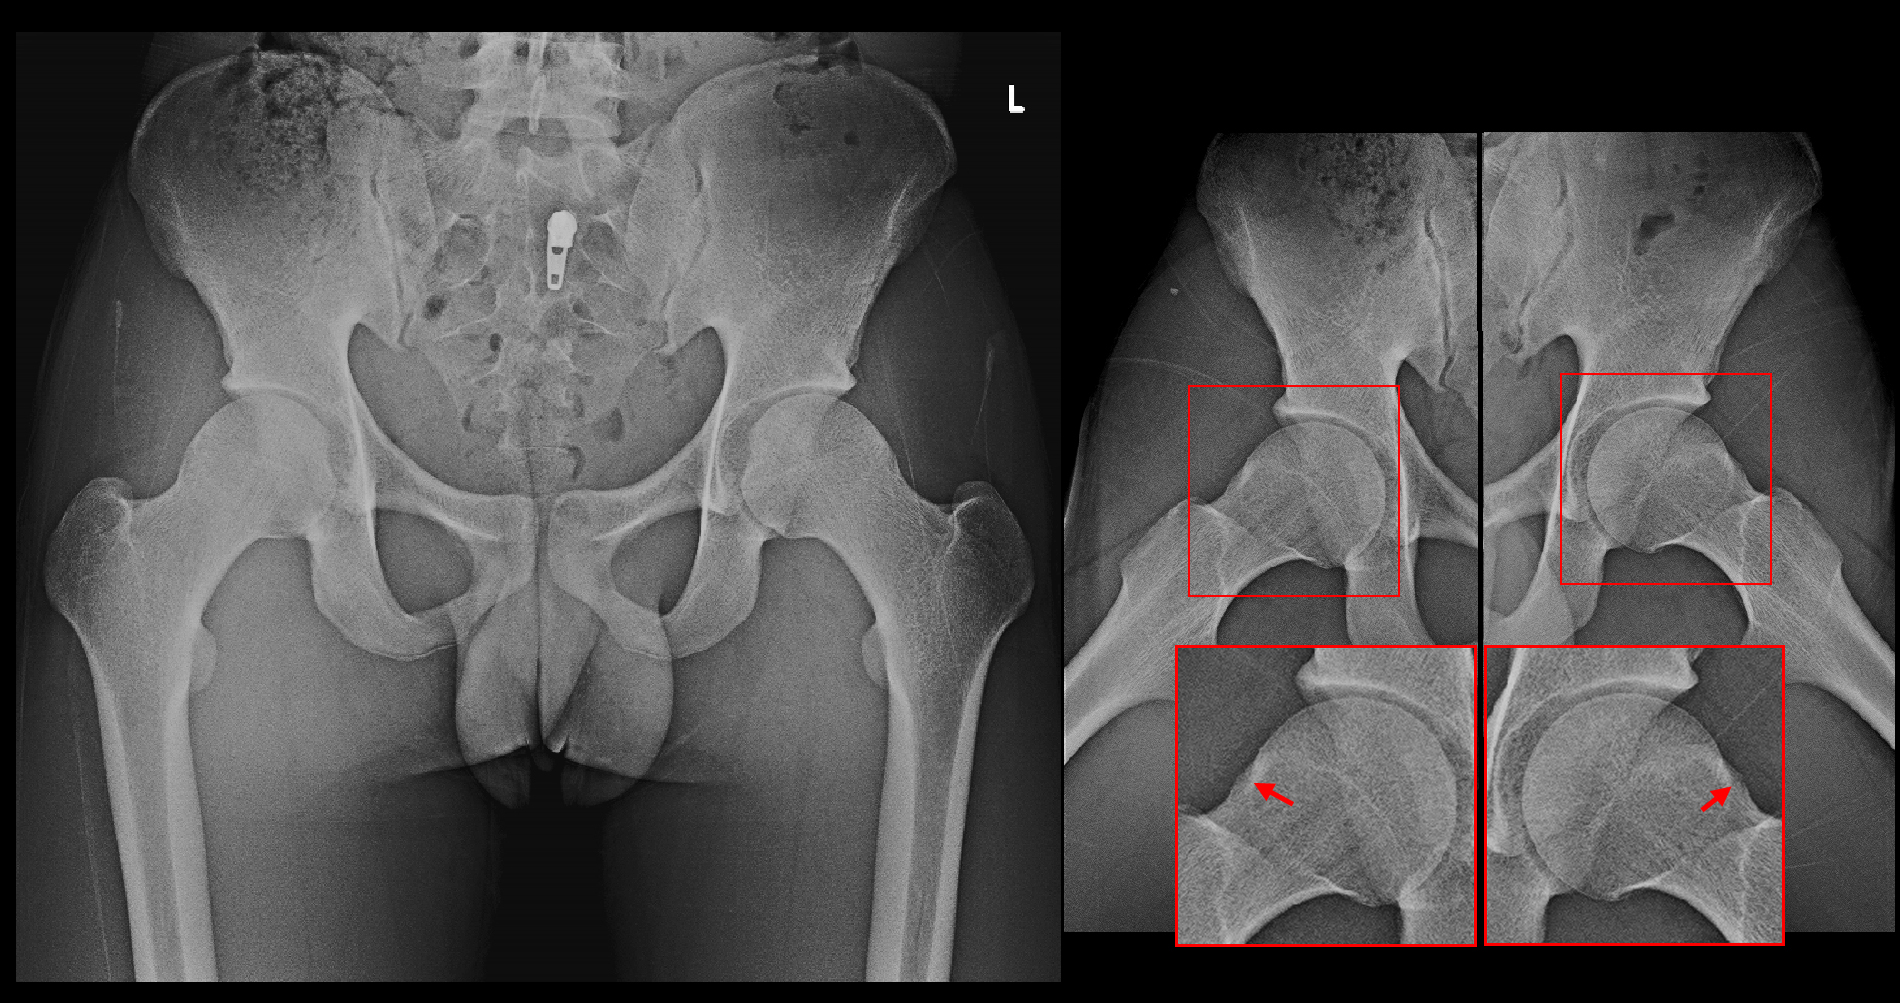

16才男Xp3.jpgS君の股関節レ線像と正常男性の股関節レ線像を比較すると、微妙ですが大腿骨頭部の外側部分が少し盛り上がっています。これがFAIの原因となります。大腿骨骨頭の外側部が盛り上がっていると、股関節を屈曲していった時にその膨隆部が臼蓋の周囲の関節唇を圧迫して損傷することになるのです。

S君はハンドボールの練習、自転車をこぐ等の股関節の屈曲の動作で関節唇が傷ついて痛みを発症させていたと推察されます。